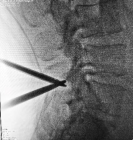

3.微创PKP技术:老年压缩性骨折球囊扩张椎体成形术

经皮球囊扩张椎体后凸成形术是性爱视频

很早就开展的一项微创技术,已经有20多年,每年手术约200例,尤其适用于老年骨质疏松引起的胸腰椎骨折;椎体转移性肿瘤(溶骨性破坏);引起疼痛症状的椎体血管瘤、多发性骨髓瘤、Kummell 症。局部麻醉,创伤小恢复快,第二天可以下床活动,迄今为止最高手术患者92岁高龄。